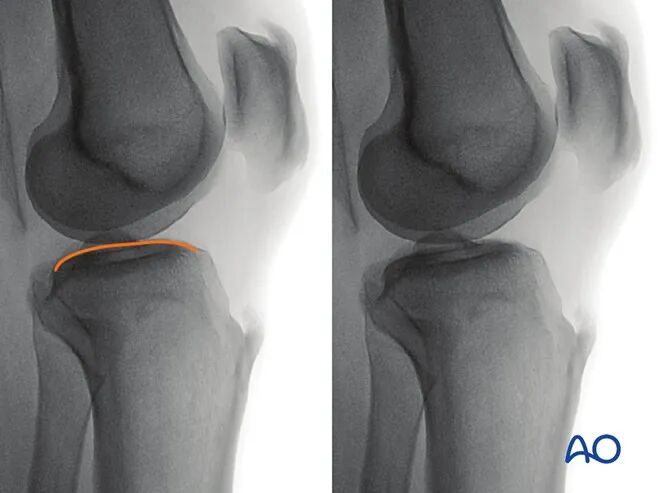

3. 胫骨近端侧位

最佳影像的验证标准

满足以下条件即为胫骨近端最佳侧位影像:

●射线束平行于胫骨关节面(或垂直于胫骨长轴);

●股骨内外髁的前、远端及后缘完全重叠;

●股骨内外髁居中显示于影像屏幕。

可识别的解剖标志与线条

胫骨近端侧位影像中可清晰识别的解剖标志与线条包括:

1.外侧胫骨平台(凸面线影)

2.内侧胫骨平台(凹面线影)

3.胫骨棘

4.胫骨结节

5.骨骺线瘢痕。

临床观察要点

该体位尤其适用于判断以下情况:

●内外侧胫骨平台复位不良;

●胫骨棘复位不良;

●胫骨平台相对于股骨的前后向半脱位(提示交叉韧带损伤);

●关节内植入物位置。